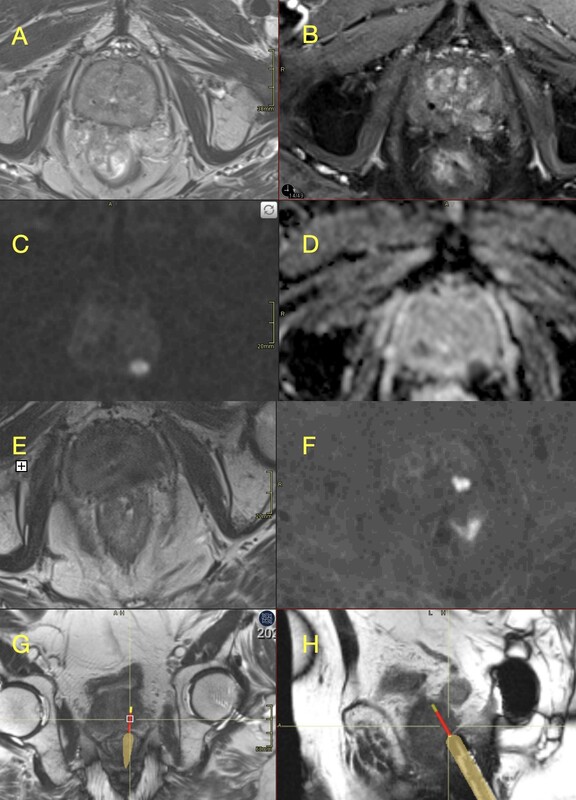

Figure 2

Example of Prostate Imaging for Recurrence Reporting (PI-RR) 4 lesion on multiparametric magnetic resonance imaging (mpMRI) with in-bore targeting (Gleason 4 + 3). A) Axial T2-weighted image showing a low-signal focal lesion in the left peripheral zone (mid-gland). B) Dynamic contrast-enhanced (DCE) imaging demonstrates early enhancement. C, D) Diffusion-weighted imaging (DWI) and corresponding apparent diffusion coefficient (ADC) map reveal diffusion restriction. E-H) In-bore MRI-guided biopsy: T2-weighted (E) and DWI (F) images for targeting; real-time T2-weighted axial (G) and sagittal (H) images during tissue sampling